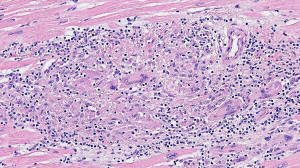

Cardiac Sarcoidosis

Figure A. H&E x 10

Clinical History: 45 year-old male with history of pulmonary sarcoidosis, atrial flutter and non ischemic dilated cardiomyopathy.

Histology: H&E sections of heart explant show various discrete, non necrotizing granulomas that are composed of nodular lesions with epithelioid histiocytes, mononuclear cells, fibroblasts and multinucleated giant cells (arrow in figure E. There is no myocyte necrosis ruling out giant cell myocarditis.